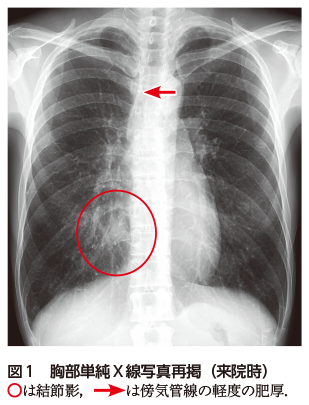

胸部の異常陰影 | 池田 貞雄 |本 | 通販 | Amazon, 解答・解説】胸部異常陰影にて紹介受診した40 歳代女性|実践!画像診断Q&A|羊土社:レジデントノート - 羊土社,

解答・解説】胸部異常陰影にて紹介受診した40 歳代女性|実践!画像診断Q&A|羊土社:レジデントノート - 羊土社, 胸部レントゲンの異常所見まとめ【保存版】※重要な疾患7つを解説 | コキュトレ,